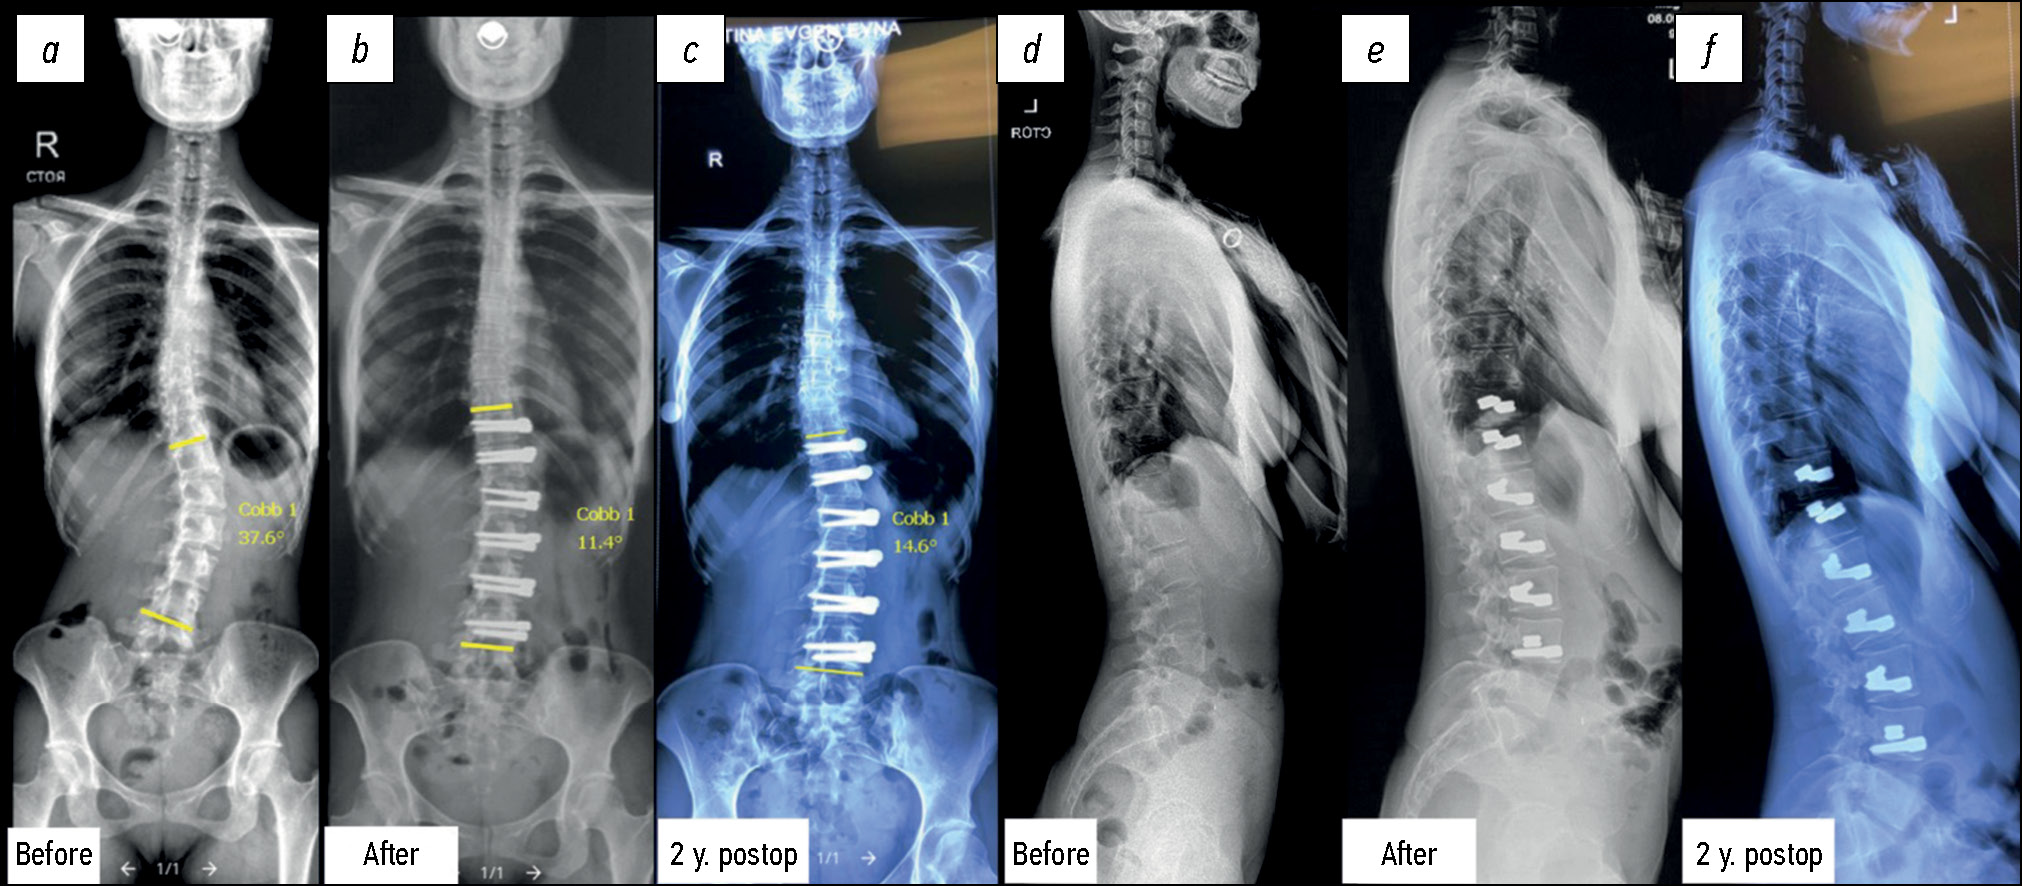

The mean Cobb angles in the thoracic ASC group at the first postoperative study and the last followup were 27.9°±5.3° and 25.2°±6.9°, respectively, compared with the preoperative value of 62.4°±10.9° (p <0.05). Patients who underwent surgery for lumbar/thoracolumbar scoliosis also demonstrated no significant loss of correction. The mean Cobb angles were 52.5°±8.4° preoperatively, 24.2°±12.4° postoperatively, and 27.2°±11.6° at the last followup (p <0.05).

The best results were achieved with both thoracic and lumbar/thoracolumbar correction (Fig. 2).

Fig. 2. X-ray of the patient before surgery (a, d), immediately after lumbar spine anterior dynamic scoliosis correction (b, e) and at the follow-up stage 2 years postop (c, f). There is no significant loss of correction.

The patients demonstrated a significant improvement in all preoperative Cobb angles immediately after the intervention. The correction was maintained in the majority of patients at followup, with a slight loss of correction observed in two patients.